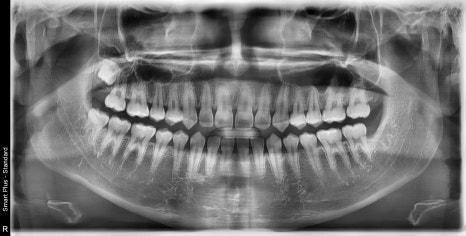

| 발치 전 | 발치 후 |